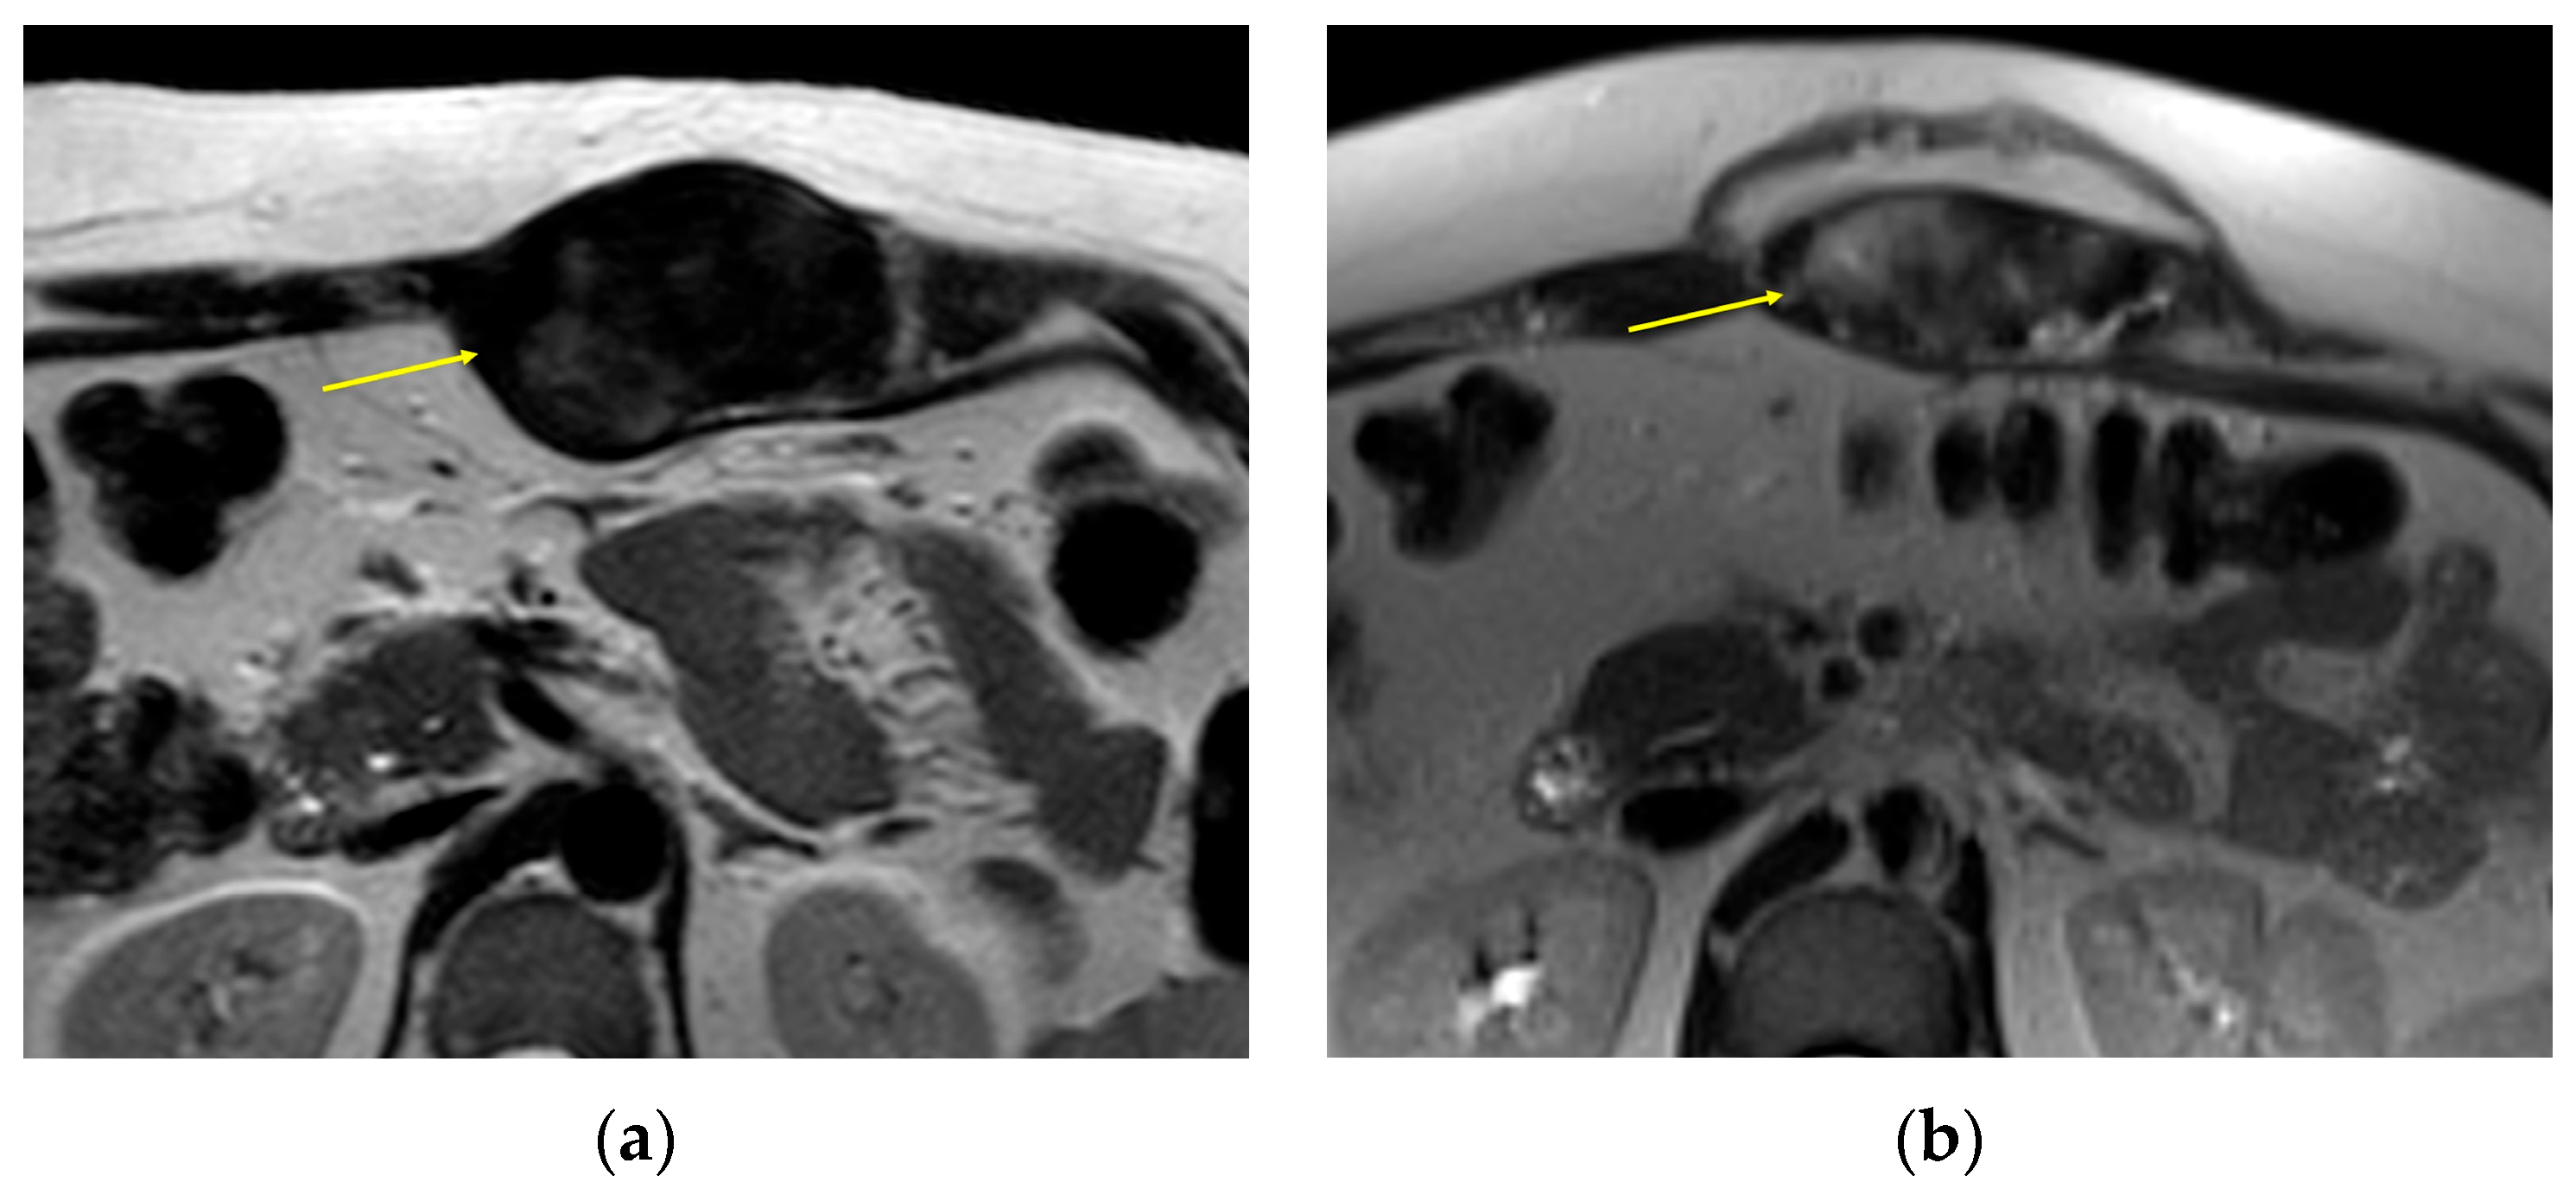

| MRI | Well-circumscribed, heterogenous with nonenhancing T1/T2 hypointense curvilinear areas related to collagen, and T1 intermediate to low/T2 intermediate to high areas related to cellularity or the myxoid matrix. Additional secondary signs (“flame”, “staghorn”, “fascial tail”, etc.) are described in text. |